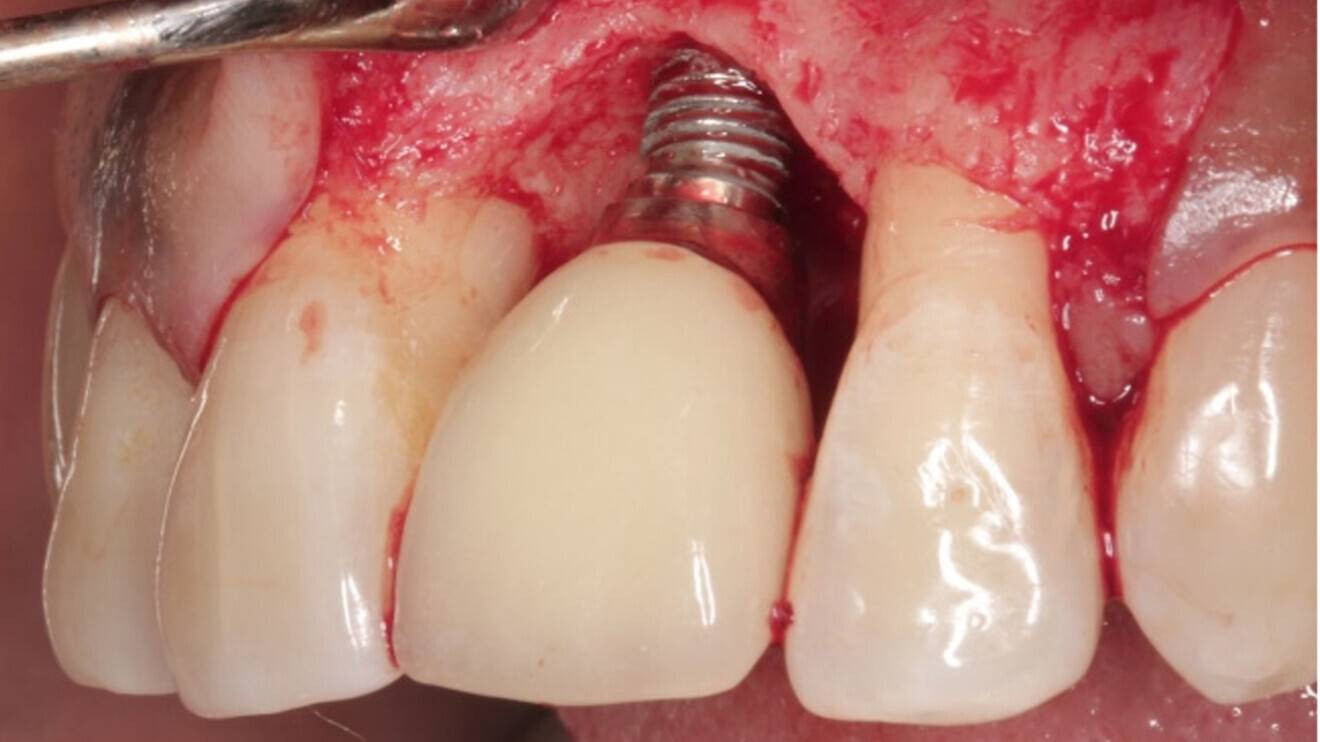

Dr Sofia Karapataki and her team monitored 39 dental implant patients with 91 Patent implants over five to 12 years and observed no cases of peri-implantitis or implant loss. (Image: Karapataki et al. 2023)

Dr Sofia Karapataki, an implantologist from Greece and the lead researcher of the study, explained that in the study researchers from the Medical University of Graz in Austria and Heinrich Heine University Düsseldorf in Germany had monitored 39 dental implant patients with 91 Patent implants over five to 12 years. Just 7.7% of patients (accounting for 9.9% of all implants) showed signs of peri-implant mucositis, she said, adding that marginal bone loss (MBL) exceeding the first thread was observed at 35.0% of mesial sites and 27.4% of distal sites. A smaller number of sites showed MBL beyond the first thread but not past the third, and there was only one instance of pocket deepening to 4 mm with bleeding, yet MBL was under 1.65 mm. There were no cases of peri-implantitis or implant loss.

According to Dr Glauser, the study confirms once again the efficacy of the Patent implant system’s potential to maintain bone stability after tooth replacement. He attributed the fostering of mature, healthy, dense and stable soft tissue witnessed by the study to the soft-tissue adhesion achieved by the Patent system in the transmucosal region, adding that a strong and intimate contact between the soft tissue and the implant surface makes it difficult for bacteria to penetrate the tissue. “The goal should be to prevent peri-implantitis from the outset—after all, prevention is the best therapy,” Dr Glauser remarked.

The Patent implant system was developed in 2003 by German implant dentists Drs Johan Feith and Wolfgang Winges. Their goal was to foster a strong soft-tissue adhesion to the implant surface that prevents bacteria from invading the peri-implant tissue via a combination of a specialised surface topography and unique soft-tissue-level design and material composition. The technology was acquired by Zircon Medical Management in 2019.